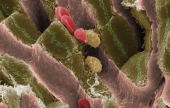

Levenhuk 870T — надежный тринокулярный биологический микроскоп, с помощью которого производится весь спектр наблюдений как в светлом, так и в темном поле. Широко используется в медучреждениях разного типа для урологических, дерматологических, биологических, биохимических, патологоанатомических, цитологических, гематологических и общеклинических лабораторных исследований. А поскольку это тринокуляр, то в комплекте с камерой-окуляром его можно без проблем использовать в качестве цифрового микроскопа. Цена: 650 000 тг. |